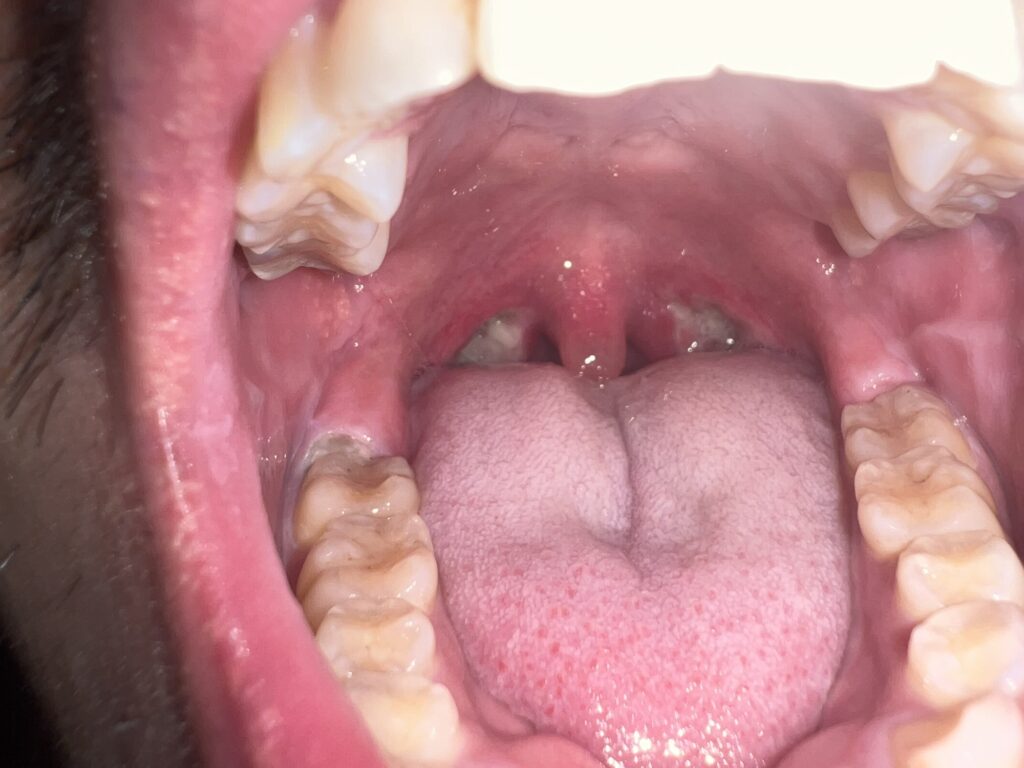

12月5日

11月6日

ほぼ完治では?!